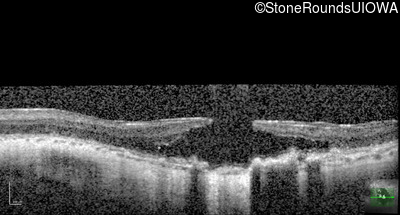

Optical Coherence Tomography - Right - Count Fingers 2'

Exemplar / OCT Stack

OCT Stack